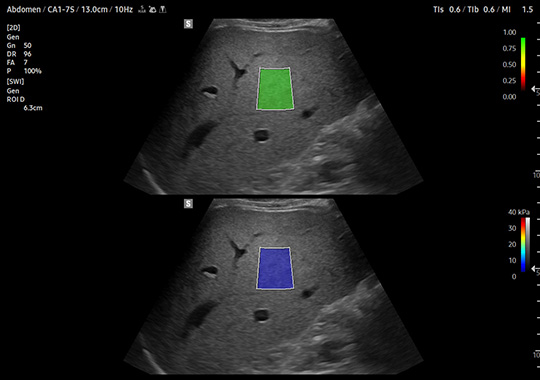

CA1-7S

- Broad Bandwidth Curved Array

- Application: Abdomen, Gynecology, Musculoskeletal, Obstetrics, Pediatric, Thoracic, Urology, Vascular